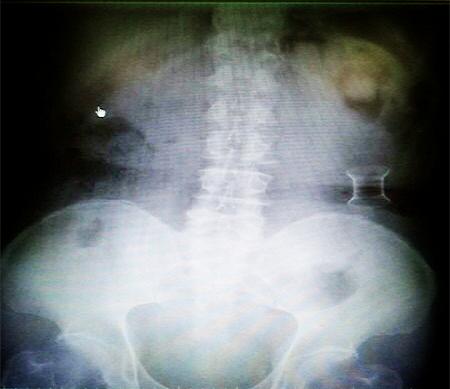

受試患者在結腸端端吻合術中,使用我司新研制產(chǎn)品達到了理想的預期效果。患者術后7天、14天X光片顯影,可降解腸道支架均能按研制設計的預期時間節(jié)點保持應有強度,術后21天X光片顯示可降解腸道支架已完全破碎,并排出體外。在整個試驗過程中,病患無任何不良反映,耐受良好。